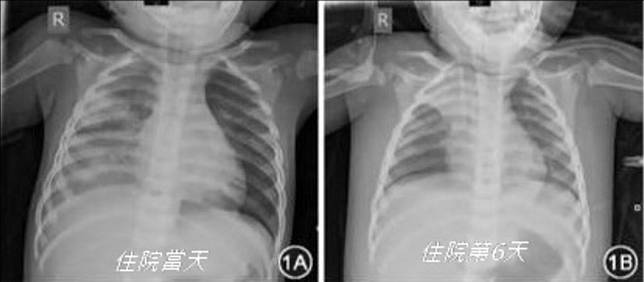

中國武漢確診武漢肺炎的1歲男童,住院短短幾天,胸部X光片顯示肺部惡化。(翻自攝陳鉉煒臉書)

陳鉉煒指出,這篇由中國醫師「陳鋒」掛名第一作者的研究報告「中國首例兒童危重型新型冠狀病毒肺炎」顯示,武漢肺炎還很狡猾,這名男嬰住院第2天、第7天採樣都陰性,直到第8天3度採樣才確診,最後入院第10天病情明顯好轉,成功脫離呼吸器。